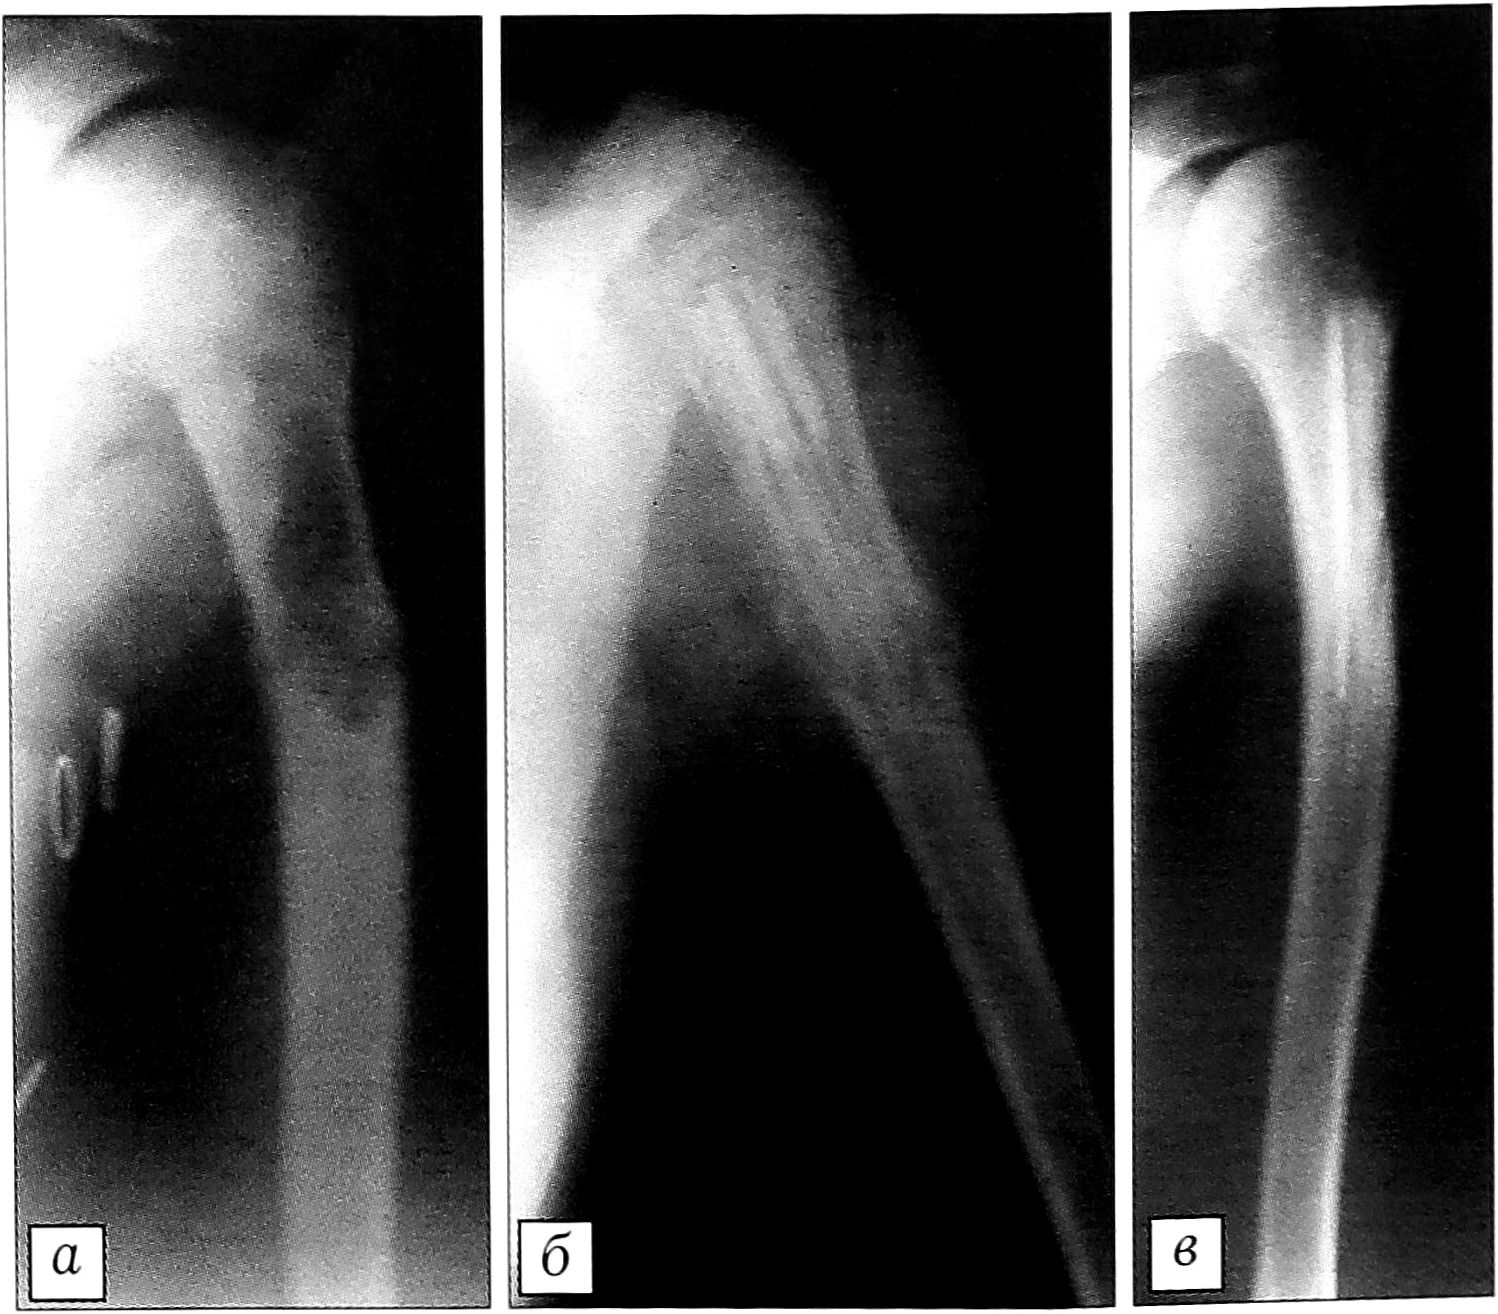

В изолированном виде «Перфоост» был использован при оперативных вмешательствах у 106 детей (солитарная киста кости — 33 случая, аневризмальная киста кости — 28, фиброзная дисплазия — 10, неоссифицирующаяся фиброма и хондробластома — по 9 случаев, болезнь Олье — 7, остеофиброзная дисплазия — 3, остеоид-остеома — 2, экзостозная хондродисплазия, гемимелическая форма эпифизарной дисплазии, юношеский эпифизеолиз головки бедренной кости, болезнь Пертеса — по одному случаю). Показаниями к применению деминерализованных аллоимплантатов у больных данной группы являлись: краевые дефекты костей верхних конечностей не более 2/3 диаметра и 1/3 длины сегмента и краевые дефекты костей нижних конечностей не более 1/3 диаметра кости [3] (рис. 1).

Рис. 1. Рентгенограммы больной Р. 12 лет. Диагноз: неоссифицирующаяся фиброма верхней трети левой плечевой кости. а — до операции; б — после краевой резекции верхней трети плечевой кости и аллопластики «Перфоостом»; в — через 12 мес после операции.